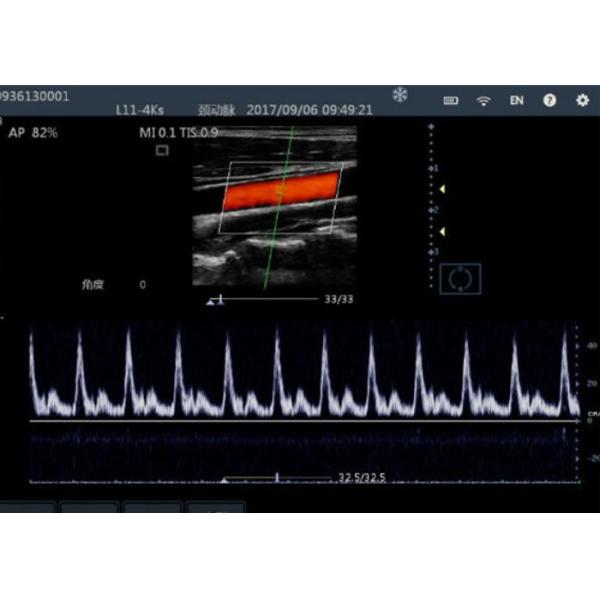

Display mode : B, B&M, 2B, 4B, THI, Color, Power, PW

| B&W mode | B, B&M, 2B, 4B, THI, Color, Power, PW |

| Digital technology | Wide-angle imaging Panoramic focusing technology Compatible with high and low speed blood Panoramic imaging Frequency compo Space compounding Rolling M technology Real-time Dynamic Aperture Tissue Harmonic Imaging Tissue Specific Imaging |

| Pre-processing | Cloud processing technology Fine blood flow imaging, high sensitivity Gain Dynamic range Persisitence M Soften Noise suppression |

| Color/Power/PW mode | D velocity, D trace, PS/ED |

| Application packages | Abdomen, Small parts, Vascular, Obstetrics,Gynecology, Cardiology, Neurology,Urology, Orthopedics, Anesthesia |

Color Doppler Ultrasound Probe Handheld Ultrasound Device For Mobilephone / PC Images |